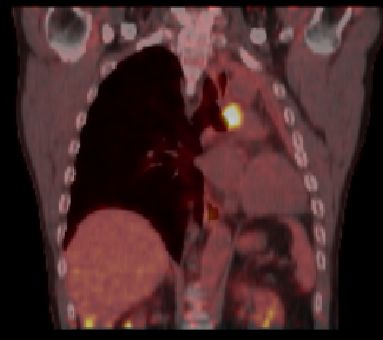

| PET-CT | 60jähriger Mann 18 Monate nach Pneumektomie links wegen Plattenepithelkarzinom des linken Lungenoberlappens pT2a pNo Mo![]() ![]() |